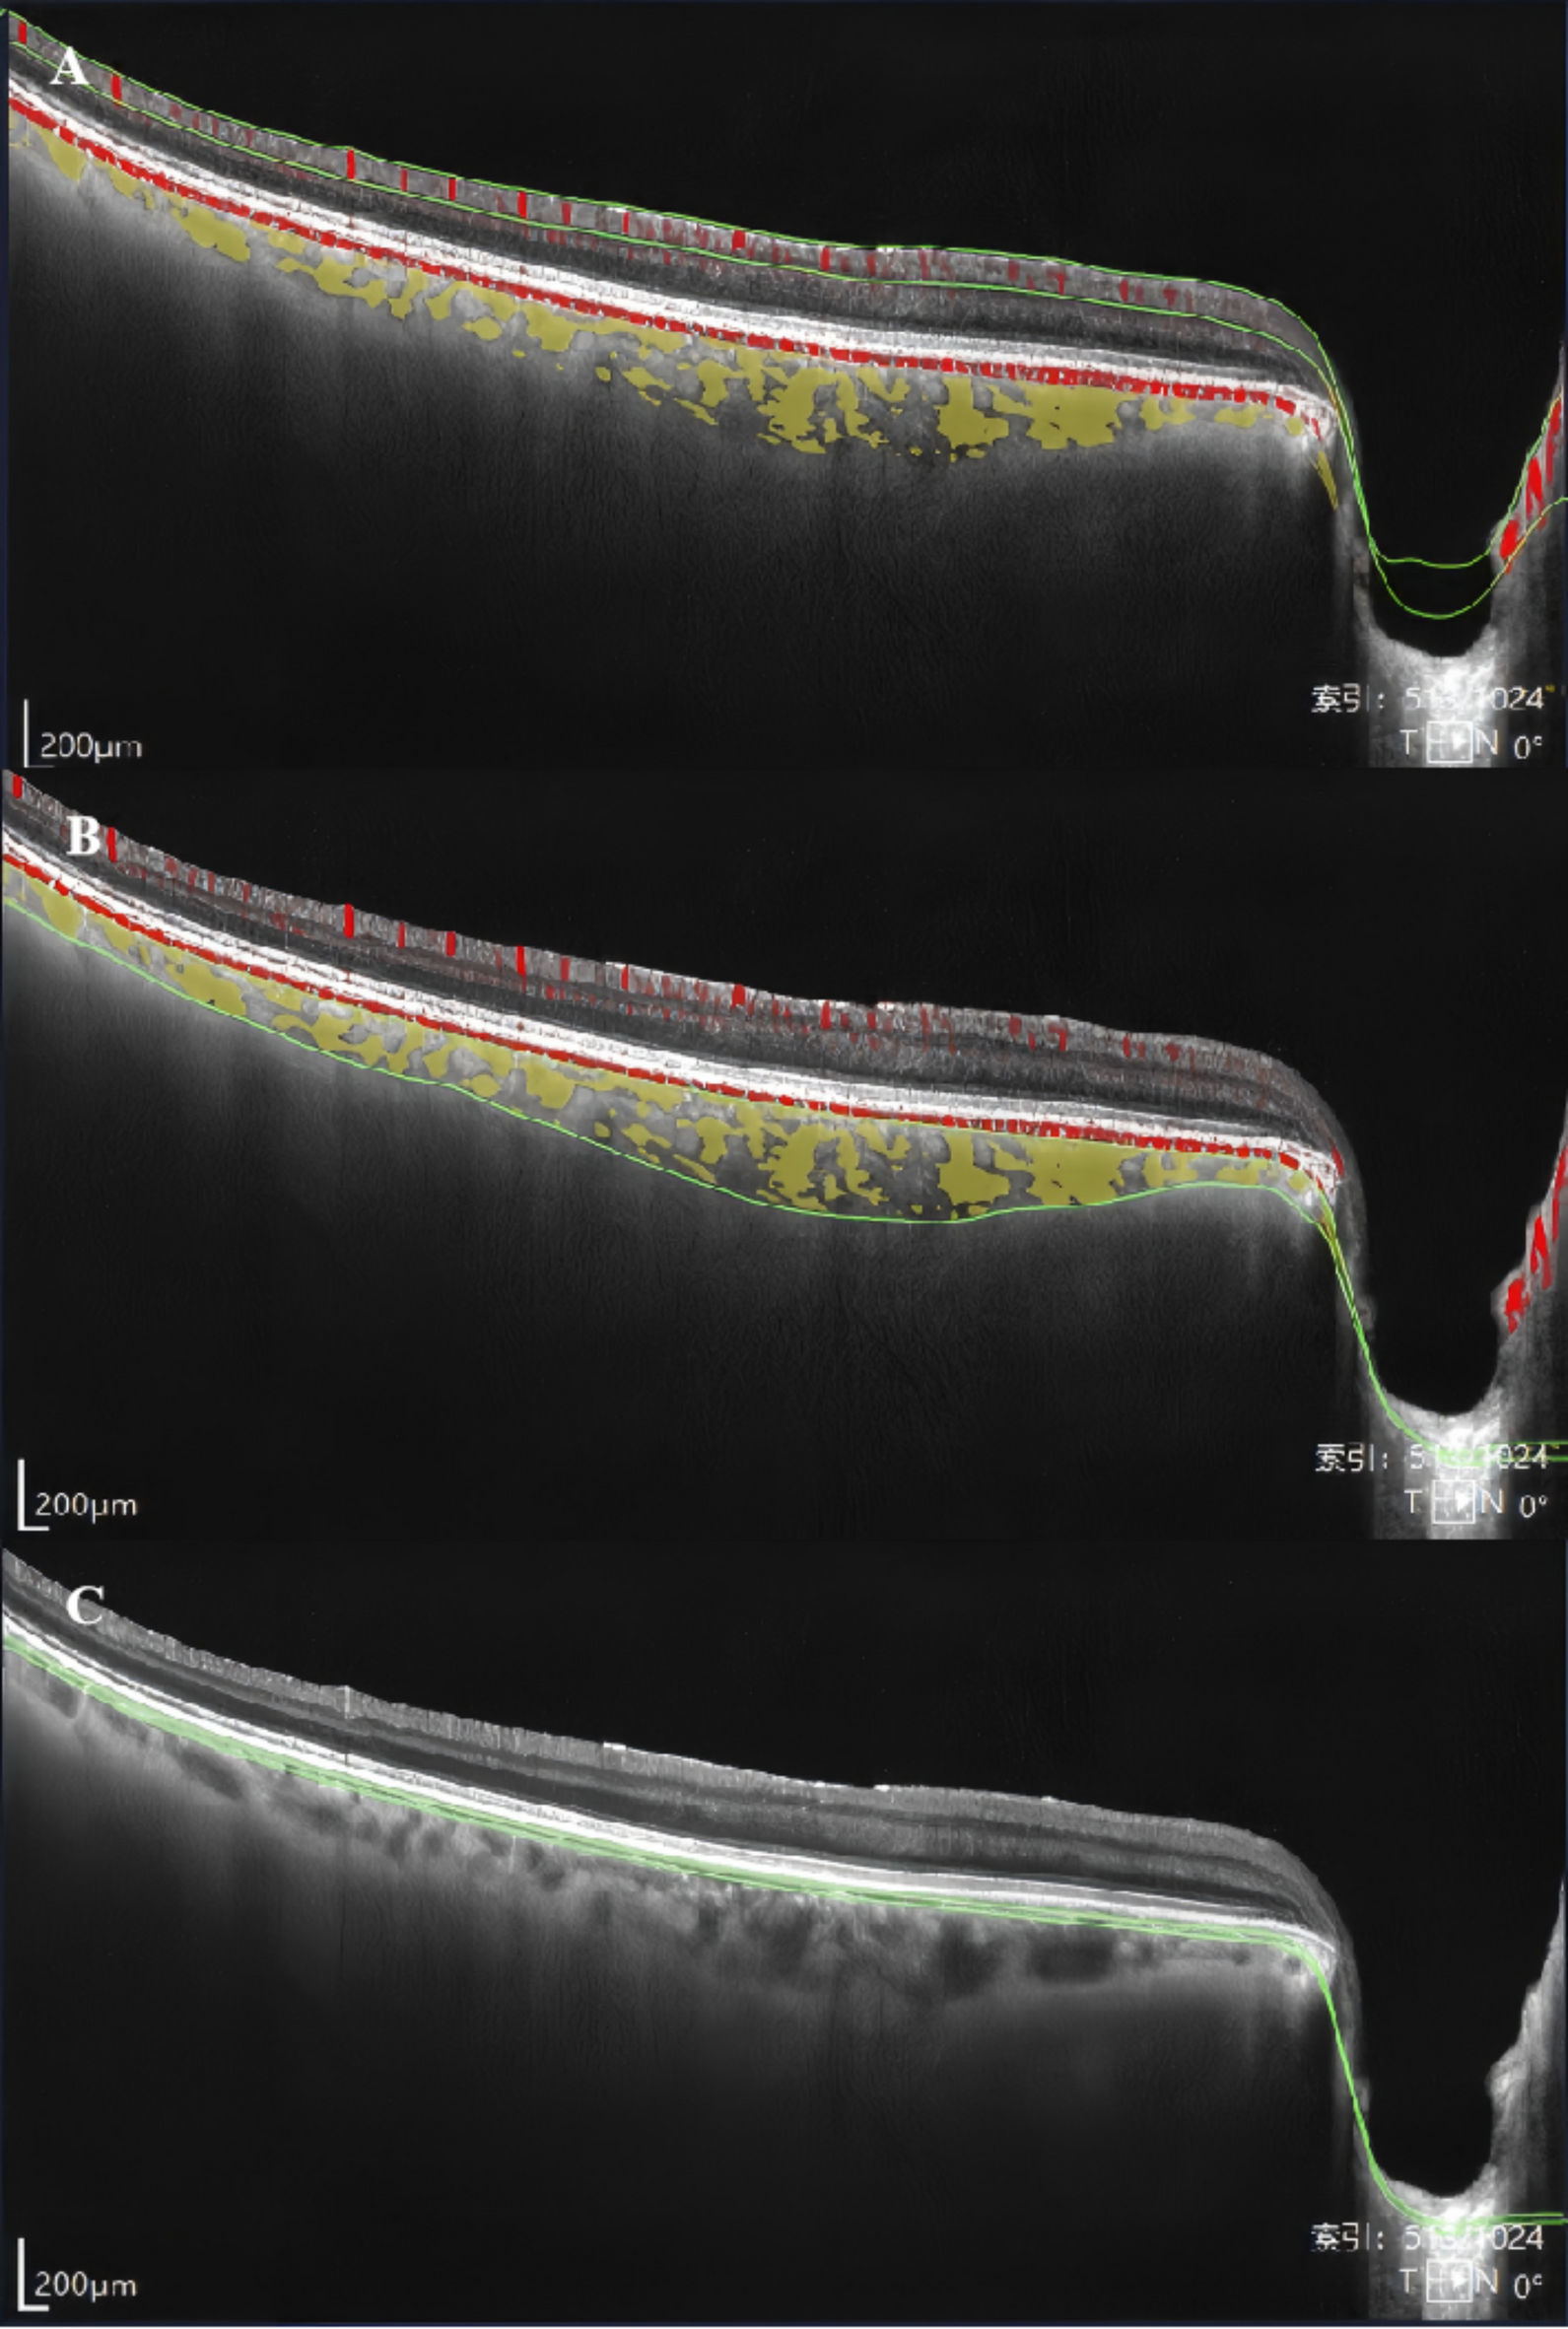

Fig. 1

Segmentation of macular subregions, structure, and microvasculature. (A) Retinal SVC, defined as the area between the two green segmentation lines. (B) LMCVL, defined as the area between the two green segmentation lines. (C) Choriocapillaris, defined as the area between the two green segmentation lines.